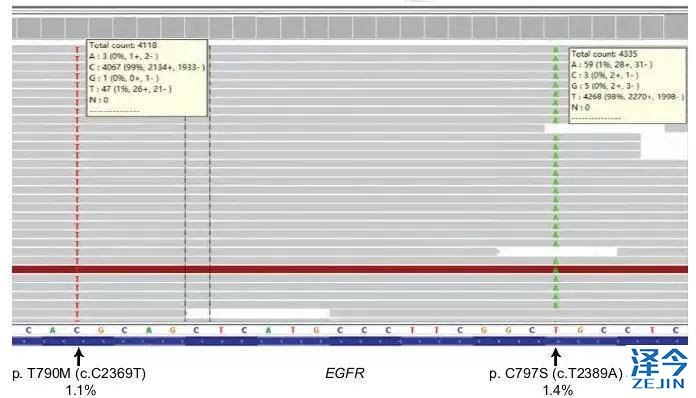

大约有30%-50%的亚洲NSCLC患者携带EGFR突变,目前1代EGFR靶向药对这类突变患者的临床疗效比传统含铂化疗的疗效更好,可以有效延长PFS。然而,大部分患者可在用药1-2年后发生耐药,主要原因为20外显子T790M的突变。针对耐药后T790M突变型患者的王牌药为奥希替尼(AZD9291)。该药可以与797位点的半胱氨酸结合来发挥作,但9291使用后常出现的C797S突变能阻断该结合位点,导致9291失效。

而C797S突变分为顺式突变和反式突变,对于反式突变,可以采用一代联三代的治疗方法。但对于顺式突变,目前还没有成熟的临床结果,最近的临床前研究证实了布加替尼联合抗EGFR抗体对C797S顺式突变的疗效。在此,小编带大家看看国内报道的首个证实布加替尼联合西妥昔单抗对EGFR、T790M和C797S顺式突变肺腺癌疗效的案例。

布加替尼联合西妥昔单抗治疗,病情长期稳定控制

患者再次基因检测发现T790M-C797S顺式突变,因此在2017年7月开始联合使用布加替尼(90mg/日)和西妥昔单抗(600mg/月),治疗一个月时,患者的疲劳和呼吸困难明显改善,CA125水平明显下降,直到2018年4月病情一直稳定(PFS为9个月),除了轻度疲劳外无其他的不良反应。虽然在2018年4月患者出现脑转移灶,但在2018年9月,患者的胸部病灶依旧得到很好的控制。